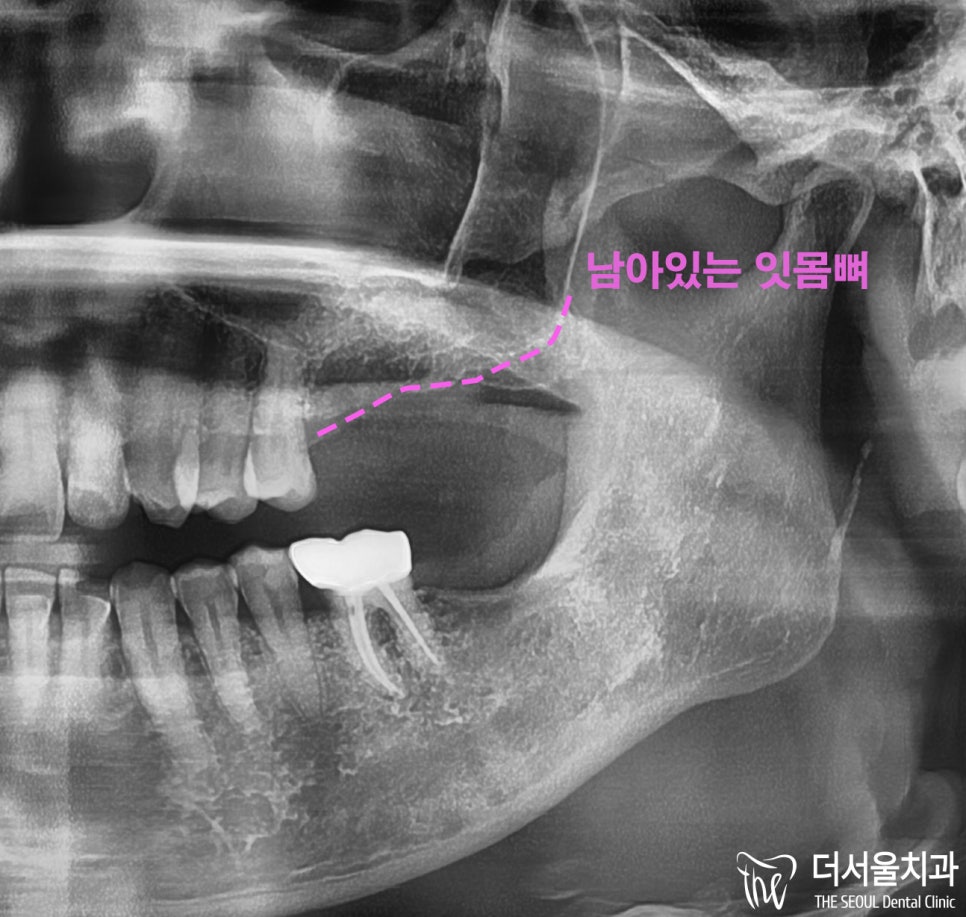

우선,

네비게이션 임플란트 를 진행하기 위해

해부학적 구조물의 위치를 파악하게 되었는데

잇몸뼈가 많이 녹아내린 관계로

상악동과 거리가 가까웠던 상황이었습니다.

상악동이 천공될 가능성이 있었으며

엎친 데 덮친 격으로

해당 구조물에 염증까지 확인되고 있었습니다.

잇몸뼈가 얼마 남지 않았는데,,

더군다나 염증까지,, 있어서 쉽지 않았습니다.